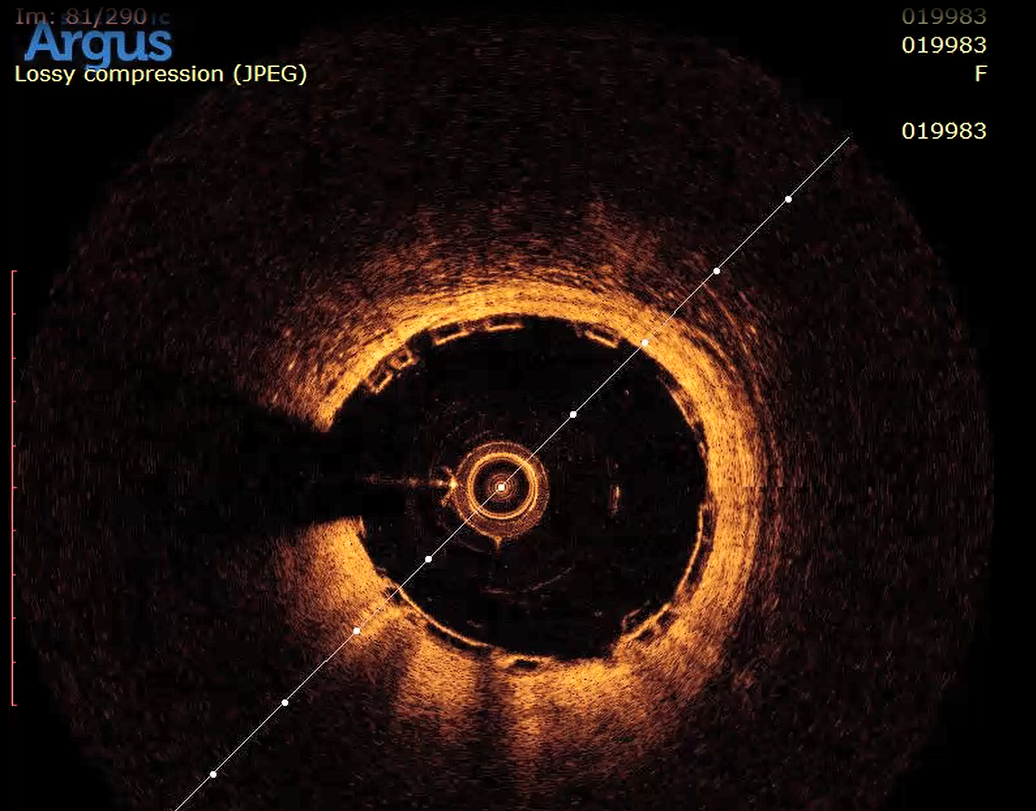

手术过程中,葛均波院士首先分别在LAD及D1各送入一根导丝。随后,为了更为精准地评价冠脉病变性质及严重程度,术者沿LAD导丝将微创阿格斯™OCT成像导管置于LAD中段,回撤成像可以清楚地看到LAD局部斑块负荷重,以纤维脂质斑块为主,管腔局部重度狭窄,病变长度25.4mm,狭窄最重处面积仅1.79mm²。

OCT示LAD中远段管腔重度狭窄,可见纤维脂质斑块